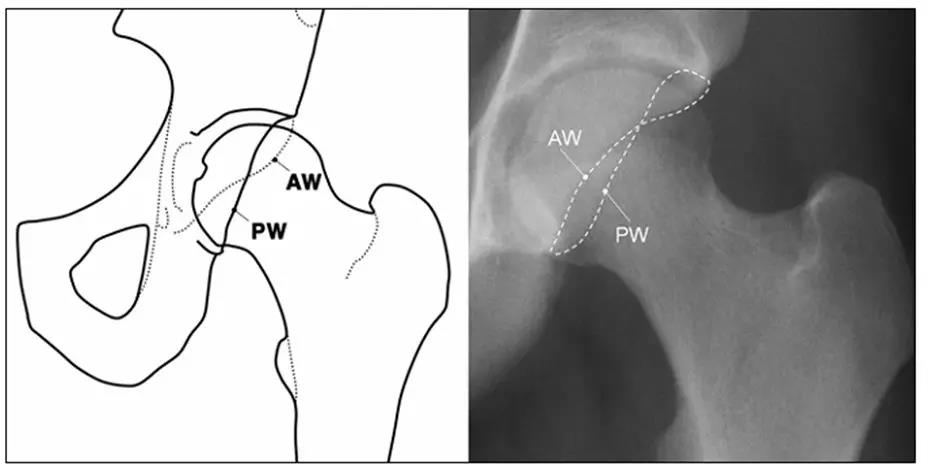

- IIL:髂坐线;AW:髋臼前壁缘;PW:髋臼后壁缘;A为股骨头被髋臼覆盖部分的宽度;E为股骨头未被髋臼覆盖部分的宽度;F为髋臼窝线。